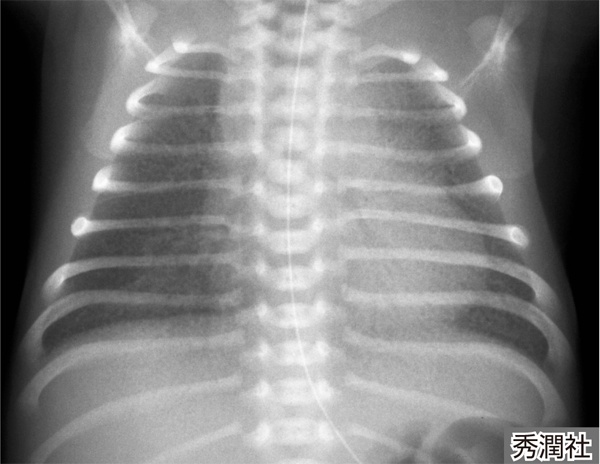

- 呼吸困難の原因について肺を研究するための胸部X線写真